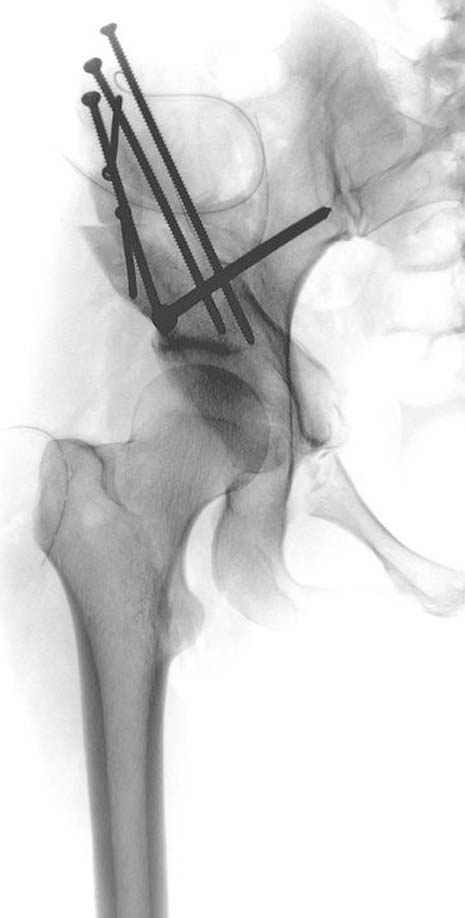

Но, занимаясь с этой патологией, собрал небольшой опыт в лечении остеоартрита, включая: периацетабулярную (ориентационно-корригирующую) остеотомию, и на проксимальной части бедра - valgus, varus, flexion and extension osteotomy и в комбинациях, базирующуюся на авангардных учениях Reinhold Ganz из Bern, на конгруентности сустава и увеличения контактной площади в суставе для уменьшения давления на площади хряща, При Вашем желании можно продемонстрировать результаты наших операций на слайдах.